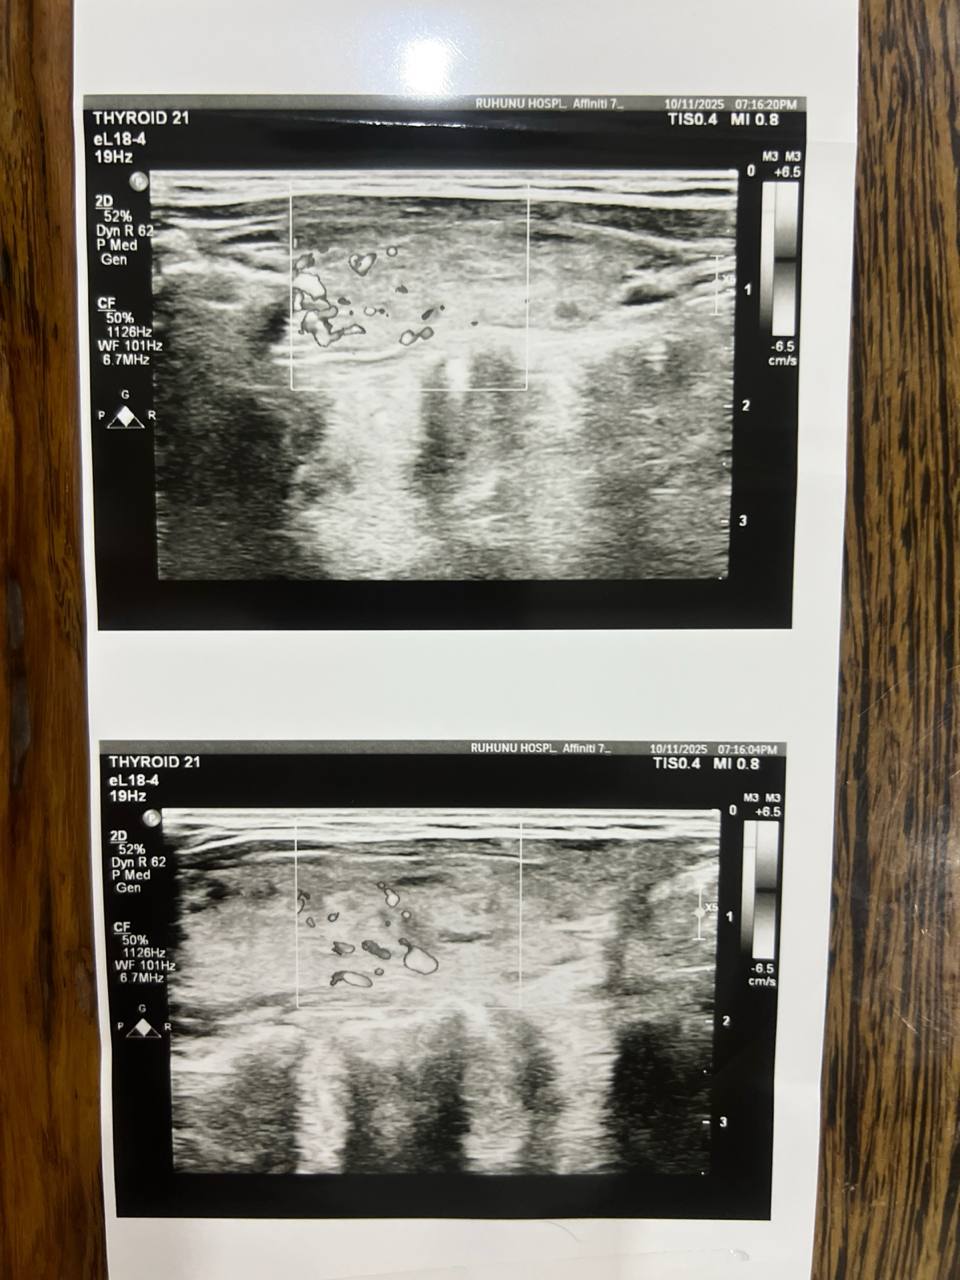

Недавно я сделала УЗИ щитовидной железы:

Незначительное увеличение правой доли щитовидной железы.

Правая доля: 5 см × 1,4 см × 2,2 см

Левая доля: 3,6 см × 0,8 см × 2 см

Очаговых узлов и зоба нет.

Подчелюстная железа в норме.

Узи расшифровал обычный врач не эндокринолог, вы разбраетесь в снимках? Скажите, подалуйста, на них соответствует картина действительности 65985464.jpg